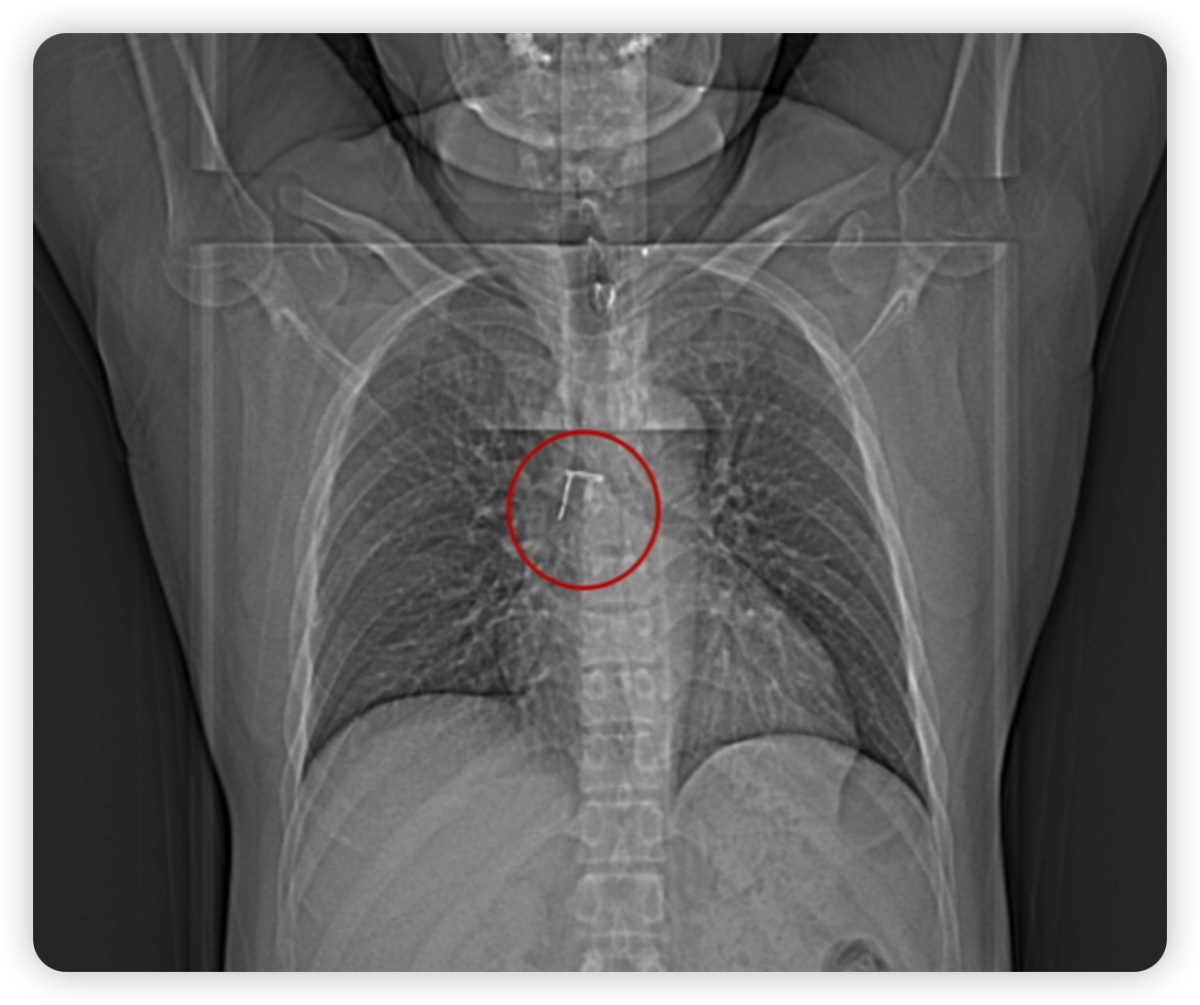

经检查,患者胸部CT提示右主支气管腔内见一“π”形高密度影,横径约18.9mm,长径约19.6mm,短径约8.0mm。

在充分评估患者病情后,结合胸部CT表现及病人异物误吸史,决定为患者行局麻下经口行支气管镜下异物取出术。

为避免气管镜操作时刺激患者剧烈咳嗽,内镜诊疗部刘薇医师及武秋菊主管护师在术前为患者进行局部麻醉,术中发现一“π”形异物卡顿于气管隆突及右主管口处,异物质地硬,似金属物,表面光滑,若贸然硬取可能会划伤患者支气管粘膜,在不断地调整角度后开始钳夹异物,气管镜缓慢移动并经过声门,最后将异物顺利取出。